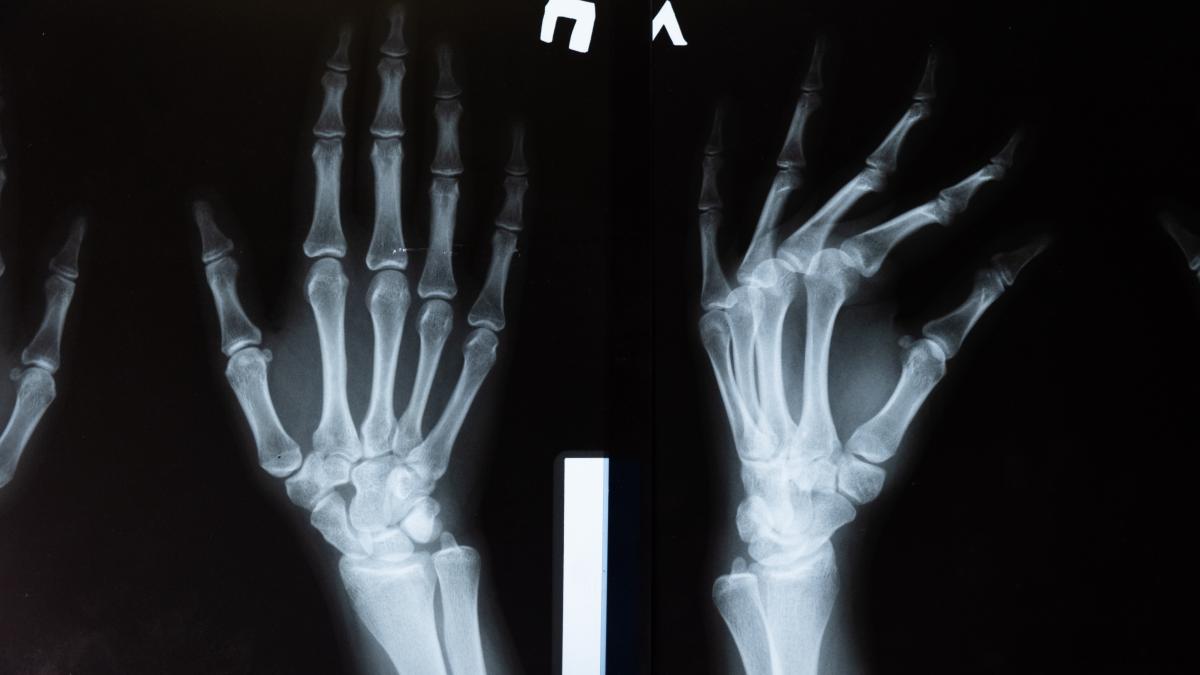

Un chirurg din Franţa ar putea fi pus sub acuzare după ce a scos la vânzare o radiografie a unei paciente, supravieţuitoare a atacului de la Teatrul Bataclan, sub formă de NFT, fără acordul acesteia.

Radiografia arată o plagă împuşcată şi un glonţ tras de un Kalashnikov în braţul femeii. Şi în anunţ era menţionat faptul că femeia fusese împuşcată în atacul de la Teatrul Bataclan, din 2015, când au murit 130 de persoane. Medicul a mai menţionat în anunţ că femeia şi-a pierdut iubitul în acel atac.